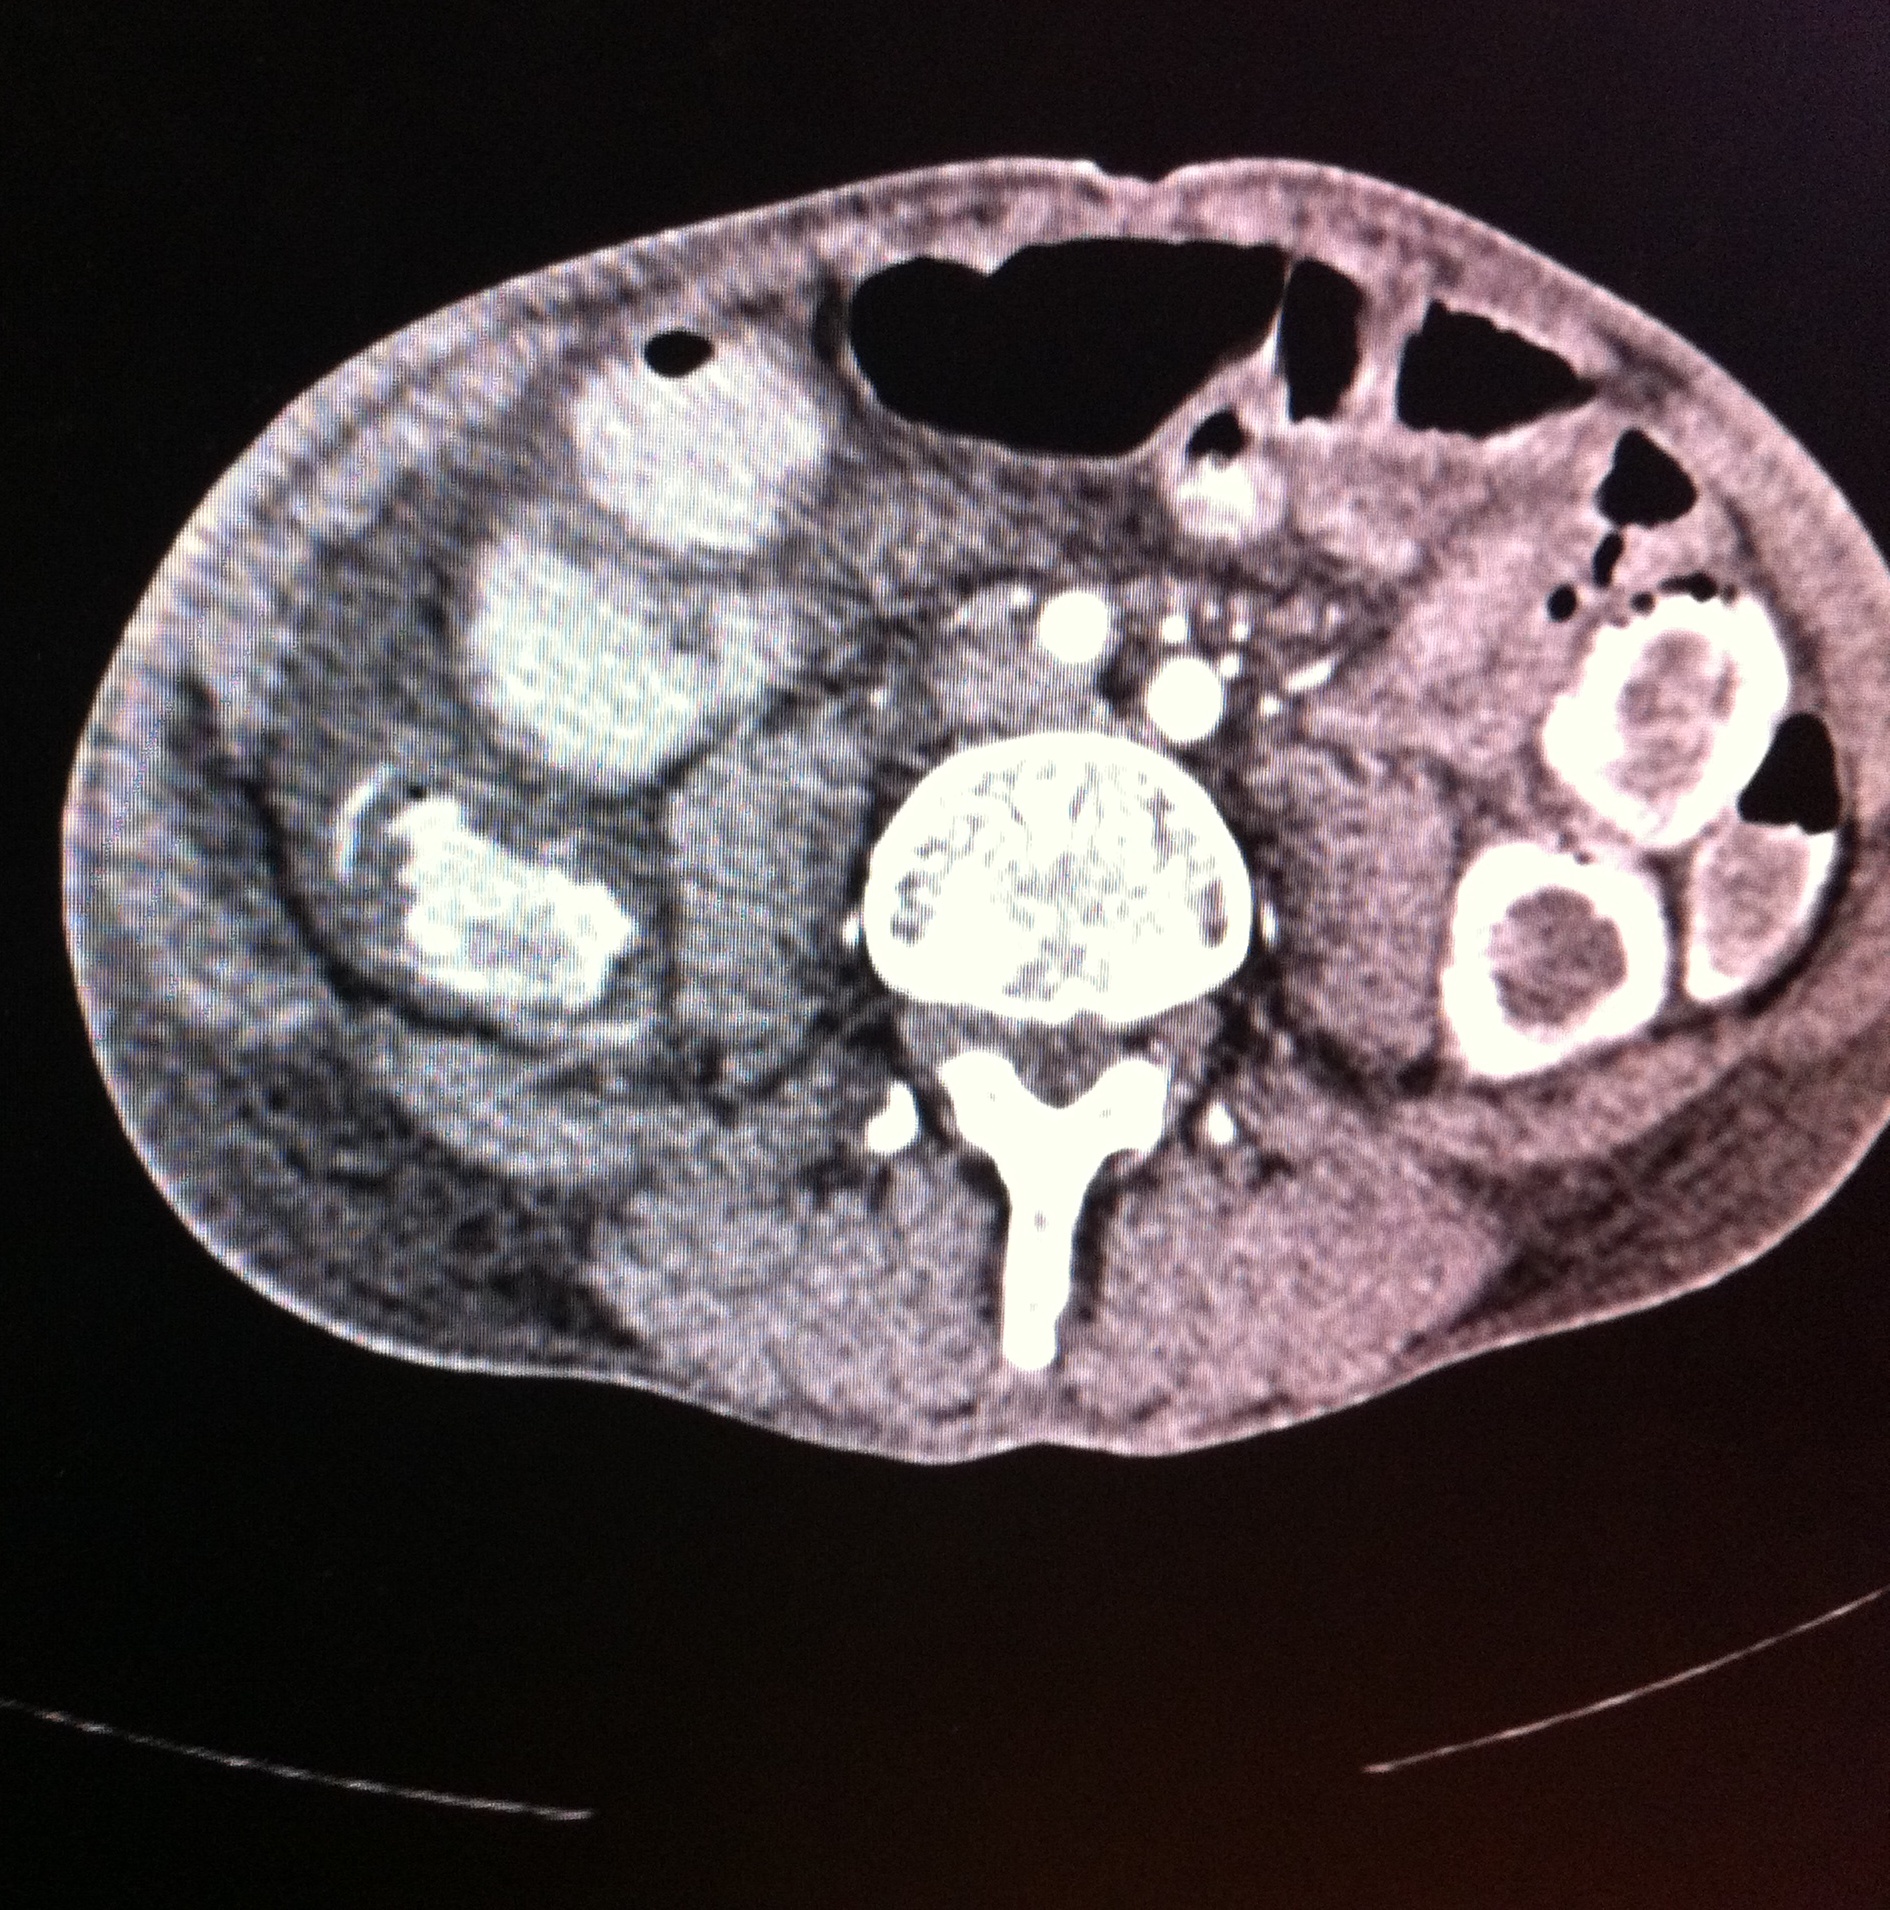

Endoscopic Retrograde Cholangio-Pancreatography (ERCP) has advantage of having bothdiagnostic and therapeutic utility and most common indication for endoscopic sphinterotomyis choledocholithiasis. Therapeutic ERCP is quite often associated with complications, mostcommon being acute pancreatitis followed by bleeding. Most common source of bleedingis small branches of pancreaticoduodenal artery (PDA) which lie close to papilla. We reporta rare case of leaking right hepatic artery pseudoanerysm following clearance of commonbile duct (CBD) stones by ERCP presenting with shock and upper GI bleed.